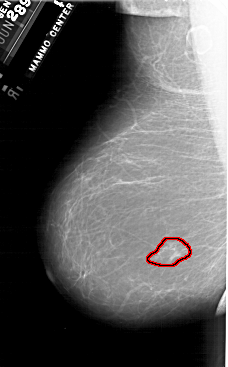

A_1902_1.LEFT_MLO

FILE: A_1902_1.LEFT_MLO.OVERLAY

TOTAL_ABNORMALITIES 1

ABNORMALITY 1

LESION_TYPE MASS SHAPE IRREGULAR MARGINS ILL_DEFINED

ASSESSMENT 4

SUBTLETY 3

PATHOLOGY MALIGNANT

TOTAL_OUTLINES 1

BOUNDARY